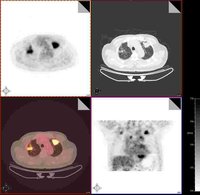

2、影像學檢查胸部X線檢查可以發現肺內病變的部位、範圍,有無空洞或空洞大小,洞壁厚薄等。X線對各類結核病變的透過度不同,通過X線檢查大致能估計結核病灶的病理性質,並能早期發現肺結核,以及判斷病情發展及治療效果,有助於決定治療方案。必須指出,不同病因引起的肺內病變,可能呈現相似的X線影像,故亦不能僅憑X線檢查輕易確定肺結核的診斷。X線攝片結合透視有助於提高診斷的準確性,可發現肋骨、縱隔、膈肌或被心臟遮蓋的細胞病灶,並能觀察心、肺、膈肌的動態。肺結核的X線表現包括:纖維鈣化的硬結病灶,表現為密度較高、邊緣清晰的斑點、條索取或者結節;浸潤性病灶,表現為密度較單,邊緣模糊的雲霧狀陰影;乾酪樣病灶,表現為密度較高,濃淡不一,有環形邊界透光區的空洞等。肺結核病灶通常在肺上部、單側或雙側,促成時間較長,且有多種不同性質的病灶混合存在及肺內播散跡象。凡X線胸片上顯示滲出性或滲出增殖性病灶、乾酪樣肺炎、乾酪樣病灶、空洞(除淨化空洞外),均提示為活動性病變;增殖性病變、纖維包裹緊密的乾酪硬結灶火及纖維鈣化灶等,均屬非活動性病變。活動性病灶的痰中仍可找到結核菌。由於肺結核病變多為混合性,在未達到完全增殖或纖維鈣化時,均仍應考慮為活動性。肺部CT檢查對於發現微小或隱蔽性病變,了解病變範圍及肺病變鑑別等方面均有幫助。

4.x 線胸片兩肺見典型粟粒陰影 。胸CT急性血行播散型肺結核表現為直徑1-3mm大小、密度及分布均勻的粟粒結節;而亞急性和慢性患者表現以上中肺野為主的3-7mm大小、密度及分布不均勻的結節。結節的邊界多數尚清晰,但也有表現邊界模糊;結節隨機分布於肺小葉、小葉間隔及胸膜下。